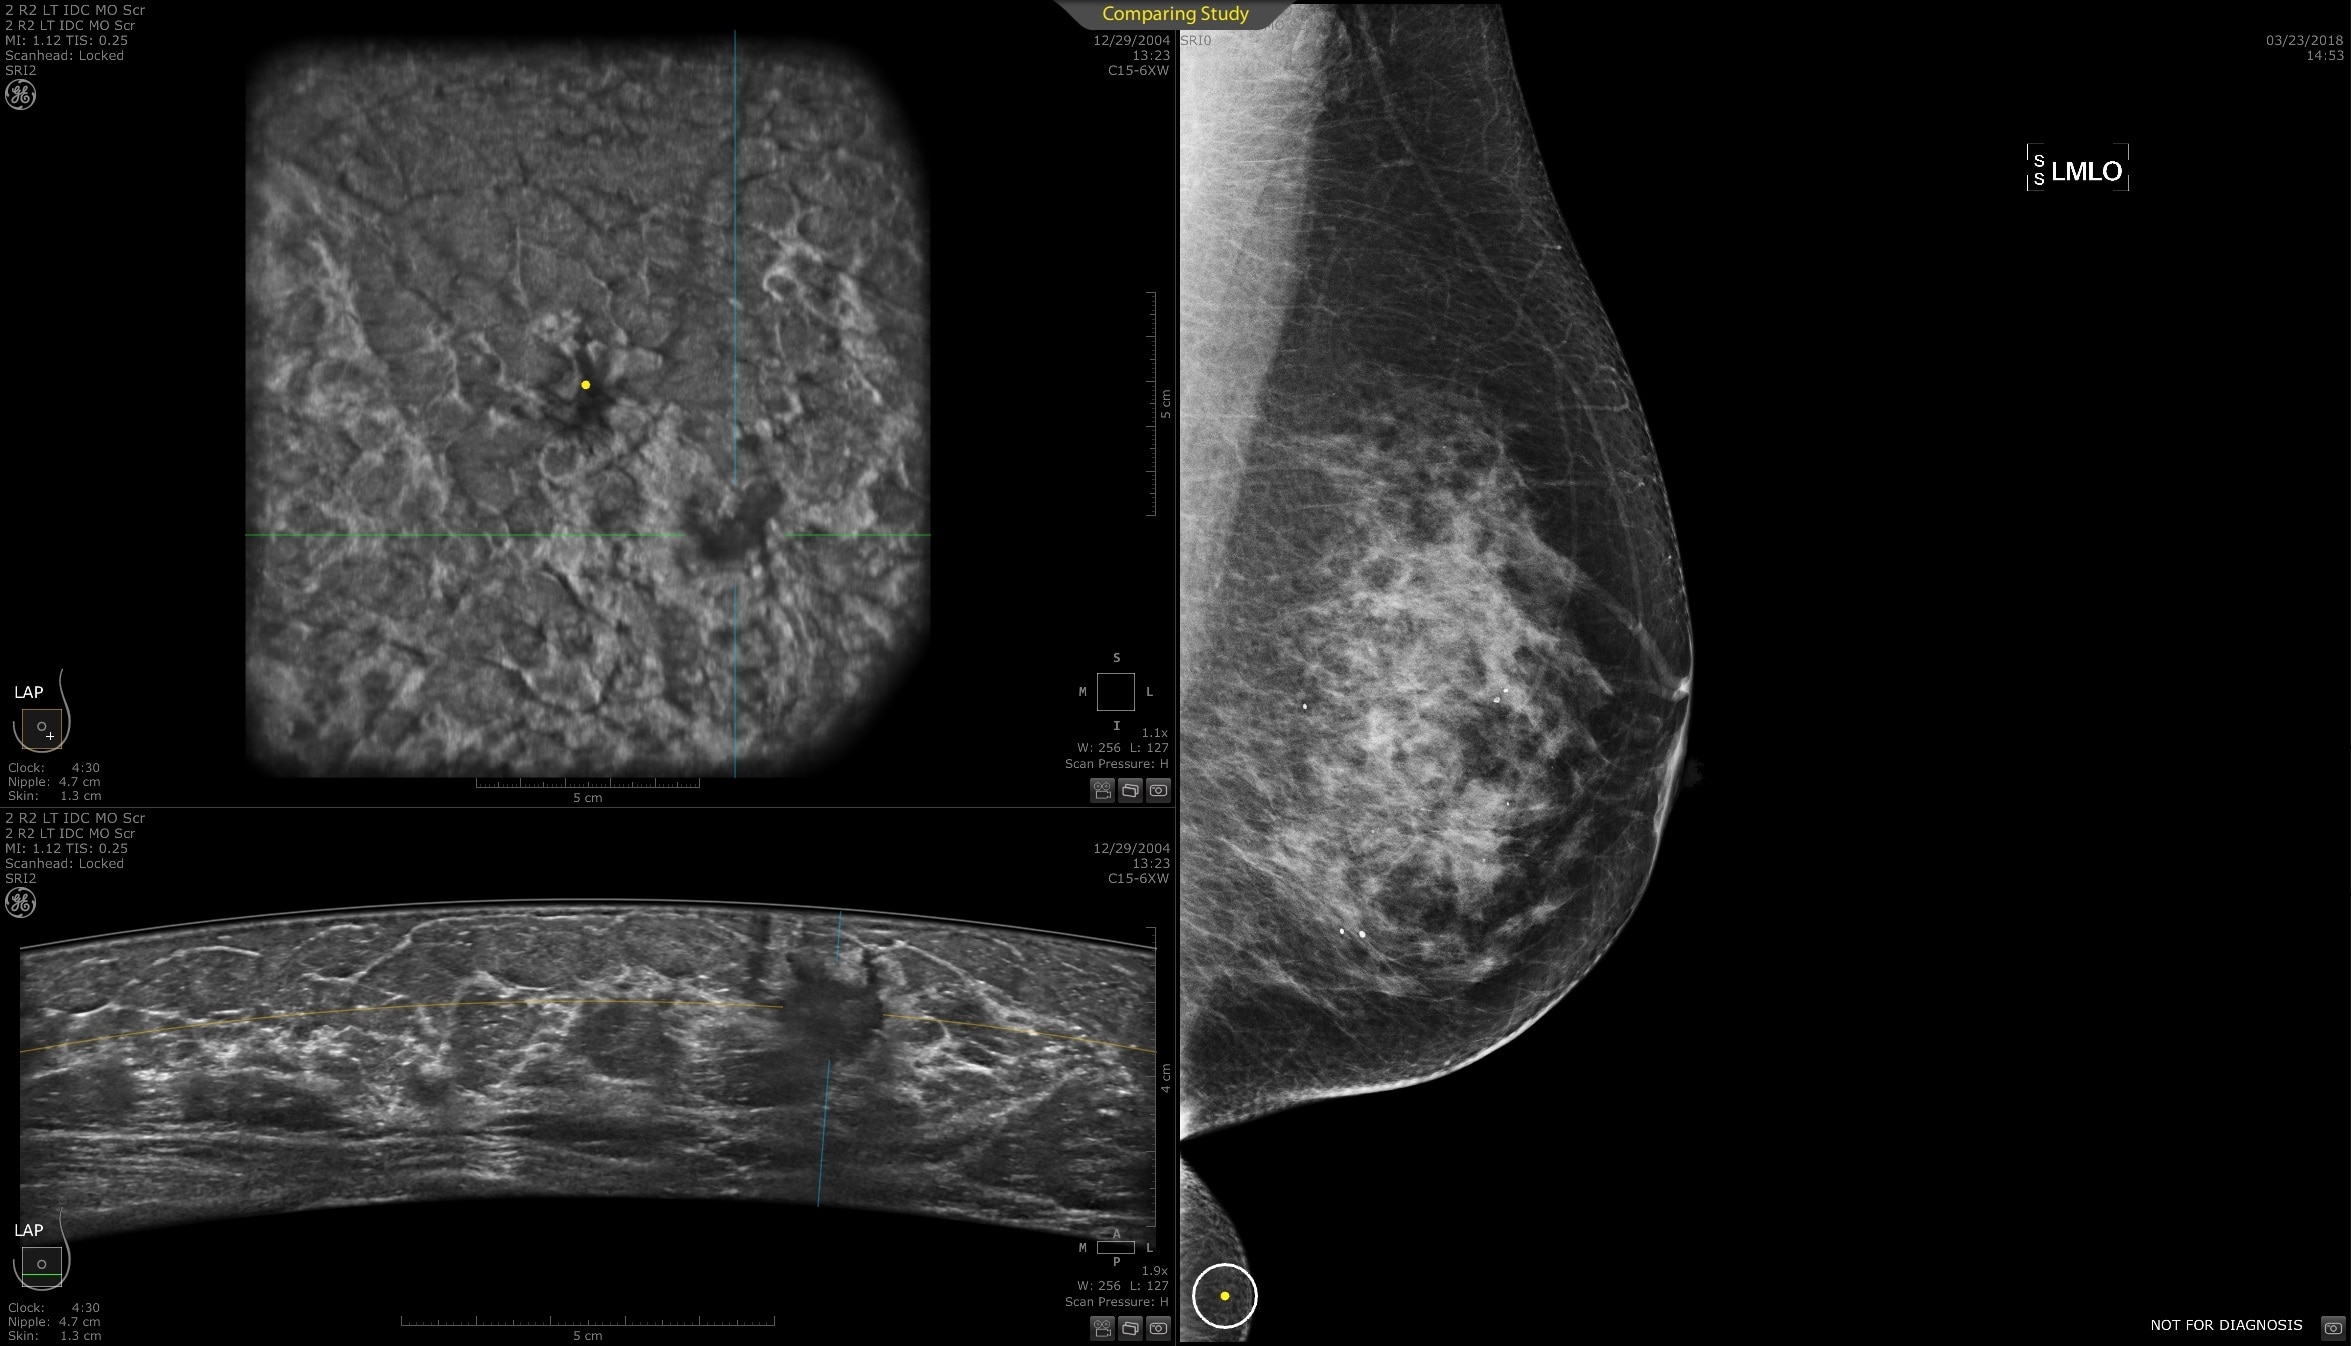

Lesion characterization for confident staging in dense breasts

Invenia ABUS 2.0 uses the latest ultrasound innovations and AI based solutions to help improve precise diagnosis and elevate clinical confidence.